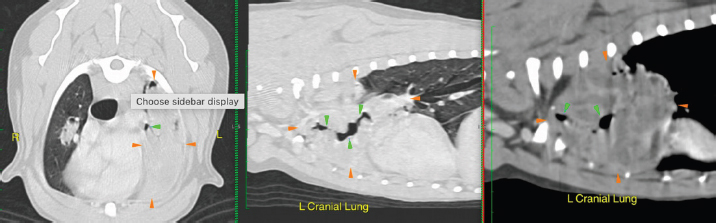

Plain and contrast CT studies of the thorax and abdomen were evaluated by a board-certified radiologist. A large, lobulated mass lesion on the left cranial lung lobe was identified that measured 7.6 × 2.1 × 5.8 (L × W × H) cm and extended to the level of the left main stem bronchus (Fig. 2). The mass surrounded, compressed and distorted all of the bronchi within the cranial subsegment of the left cranial lung and exhibited heterogeneous contrast enhancement with a few non-enhancing fluid pockets. At the right cranial and middle lung lobe, there was irregular nodular thickening which infiltrated into the lumen of the lobar and secondary bronchi, distorting the contour of the airway and causing near complete occlusion and distortion of the airway (Fig. 2). Similar irregular soft tissue thickening was identified in the lobar bronchus of the right middle lung lobe, extending through the distal branches and causing complete occlusion and distortion of the airway (Fig. 2). The sternal lymph node was moderately thickened, measuring approximately 1.1 cm in thickness (Fig. 3). The distinction between the sternal lymph node and the left cranial pulmonary mass was difficult, and it is possible that there was a direct invasion of the mass through the mediastinum pleura. A cranial mediastinal lymph node was moderately thickened and rounded, measuring approximately 1.0 cm (Fig. 3). Remaining lung lobes were well-inflated with no additional soft tissue lesions. CT scan of the abdomen was unremarkable.

Fig. 2. CT scan of the thorax showing an extensive lesion suspected to be a mass affecting the left cranial and middle pulmonary lobes causing distorted narrowed airways. Orange arrowheads demarcate the mass and green arrowheads demarcate the airways.